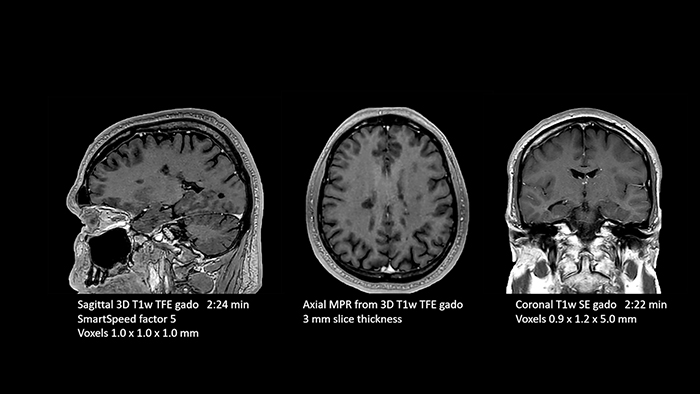

- White matter lesions in brain

In this examination SmartSpeed is used to reduce scan times. All three FLAIR orientations were obtained with only one 3D sequence using SmartSpeed. Performed with 1.5T Ambition X, dS Head coil.

- White matter lesions in brain

In this examination SmartSpeed is used to reduce scan times. All three FLAIR orientations were obtained with only one 3D sequence using SmartSpeed. Performed with 1.5T Ambition X, dS Head coil.